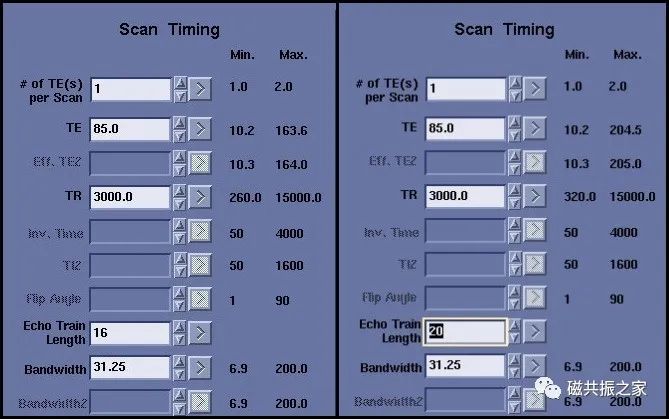

回波链

回波链并不是越长越好,虽然一定长的回波链会减少扫描时间(并不是ETL越长,时间越短),但回波链的延长会引起TE值的延长(下图回波链16与20的区别),回波间隔的增加则引起图像模糊。同样长回波链会降低图像的信噪比。

同时回波链并不是越短图像就会越好,短的回波链会降低图像的T2对比(如长T2成像)。所以回波链应选取一个适当的值,这里要考虑的因素很多。通常T1WI:2-3个;PDWI:8-12个;T2WI:10-16个,但这不是绝对的,如果第一个回波时间值加上最后一个回波时间值的和除以2后的值与当前设置的TE值接近,那就是比较合适的。